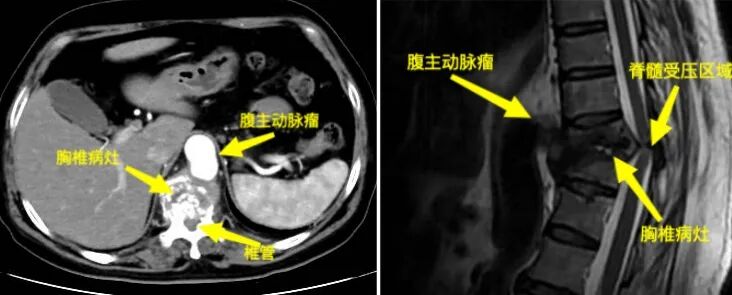

近日,在貴陽市公共衛(wèi)生救治中心骨外科與貴州醫(yī)科大學(xué)附屬醫(yī)院血管外科的攜手合作下,成功完成了一例胸椎結(jié)核合并下肢不完全性癱瘓以及胸腹主動(dòng)脈瘤的復(fù)雜病例,并且患者已康復(fù)出院。此次病例的成功救治進(jìn)一步加深了兩院之間的學(xué)科合作,并為處理類似復(fù)雜疑難病癥的多學(xué)科診療模式積累了寶貴經(jīng)驗(yàn)。 患者因“腰背痛并伴有下肢無力,導(dǎo)致無法正常行走長(zhǎng)達(dá)一個(gè)月”前往貴陽市公共衛(wèi)生救治中心骨外科就診。經(jīng)過詳細(xì)檢查,患者的下肢肌力評(píng)分僅達(dá)到3級(jí),且在臍水平面以下區(qū)域感覺明顯減退,無法站立和行走。結(jié)合影像學(xué)檢查結(jié)果,醫(yī)生考慮患者可能患有胸9-11椎體結(jié)核。進(jìn)一步檢查還發(fā)現(xiàn)患者存在腹主動(dòng)脈上段假性動(dòng)脈瘤,并且該動(dòng)脈瘤與胸9-11椎體結(jié)核病灶緊密相連。這使得胸椎手術(shù)面臨術(shù)中大出血的風(fēng)險(xiǎn)(圖1-4)。

圖1.圖2:術(shù)前見腹主動(dòng)脈瘤與胸9-11椎體病灶緊密相連 圖3.圖4:動(dòng)脈瘤術(shù)前三維影像 面對(duì)這一復(fù)雜病情,貴陽市公共衛(wèi)生救治中心骨外科迅速與貴州醫(yī)科大學(xué)附屬醫(yī)院血管外科進(jìn)行溝通,共同決定采取聯(lián)合手術(shù)治療方案。在兩家單位共同努力下,患者成功進(jìn)行了降主動(dòng)脈-腹主動(dòng)脈覆膜支架腔內(nèi)隔絕術(shù)。手術(shù)后,患者的腹主動(dòng)脈瘤得到了有效控制,血管外科團(tuán)隊(duì)也順利完成了血管修復(fù)工作(圖5-6)。 圖5.圖6:降主動(dòng)脈-腹主動(dòng)脈覆膜支架腔內(nèi)隔絕術(shù)術(shù)后 隨后,貴陽市公共衛(wèi)生救治中心骨外科對(duì)患者實(shí)施了“胸椎結(jié)核病灶清除+椎體次全切除+鈦籠植骨融合+椎弓根螺釘內(nèi)固定術(shù)”(圖7-11)。手術(shù)成功地完成了胸椎結(jié)核病灶的清除,并進(jìn)行了脊柱的重建。目前,患者已經(jīng)能夠下地行走,下肢的感覺也得到了恢復(fù)。 圖7.圖8.圖9:胸椎結(jié)核術(shù)后影像 圖10.圖11:術(shù)后三維影像 “患有腹主動(dòng)脈瘤和胸椎結(jié)核的病人相對(duì)罕見,治療過程復(fù)雜且手術(shù)風(fēng)險(xiǎn)高,需要多學(xué)科的緊密合作。這次病例的成功治療,充分體現(xiàn)了貴陽市公共衛(wèi)生救治中心骨外科與貴州醫(yī)科大學(xué)附屬醫(yī)院血管外科之間的高效醫(yī)療協(xié)作和專業(yè)實(shí)力,同時(shí)也為處理類似復(fù)雜疾病提供了珍貴的臨床經(jīng)驗(yàn)?!辟F陽市公共衛(wèi)生救治中心骨外科脊柱組組長(zhǎng)任鵬醫(yī)師表示,“跨學(xué)科的聯(lián)合治療,能夠很好地應(yīng)對(duì)復(fù)雜病情,提高治療的成功率,切實(shí)為人民群眾提供安全優(yōu)質(zhì)的服務(wù)?!?/p> 貴陽市公共衛(wèi)生救治中心骨外科簡(jiǎn)介 貴陽市公共衛(wèi)生救治中心外一科(骨外科)成立于2009年11月,是省內(nèi)唯一的骨與關(guān)節(jié)結(jié)核??萍案腥竟强?。在過去的十年中,成功治療了約4500例骨結(jié)核患者,診療效果和服務(wù)享有較好口碑。目前,科室已擴(kuò)展為三個(gè)亞??平M:脊柱組、關(guān)節(jié)創(chuàng)傷組和頭頸外科組。開展脊柱、關(guān)節(jié)等骨感染疾病、頸部疾病以及骨折、脊柱關(guān)節(jié)退行性疾病、骨腫瘤手術(shù)等治療。此外,科室還負(fù)責(zé)HIV相關(guān)骨科疾病的診治工作。 患者可根據(jù)個(gè)人需求選擇骨科專家門診或普通門診服務(wù),骨外科提供全天候24小時(shí)的醫(yī)療服務(wù)。目前,科室開展了一系列具有挑戰(zhàn)性的手術(shù)治療,包括復(fù)雜脊柱(頸胸腰)、關(guān)節(jié)結(jié)核手術(shù)、四肢關(guān)節(jié)創(chuàng)傷及椎體成形術(shù)、初次人工全髖關(guān)節(jié)置換術(shù)、初次復(fù)雜及人工髖關(guān)節(jié)翻修術(shù)、初次人工膝關(guān)節(jié)置換術(shù)、復(fù)雜初次及人工膝關(guān)節(jié)翻修術(shù)、嚴(yán)重粉碎性骨盆及髖臼骨折等。此外,科室還涵蓋綜合醫(yī)院骨科大部分常見、多發(fā)疾病的手術(shù)及保守治療??剖遗鋫淞酥行虲臂X光機(jī)、電動(dòng)磨鉆、骨折治療儀、中頻/低頻治療儀、下肢CPM功能鍛煉器、空氣壓力波等多種先進(jìn)設(shè)備。針對(duì)脊柱、關(guān)節(jié)疾病患者的主要臨床癥狀,如頸肩疼痛、腰腿疼痛、四肢關(guān)節(jié)疼痛、下肢活動(dòng)障礙等,科室還開展了中藥穴位貼敷、藥棒穴位按摩、艾灸等特色中醫(yī)治療,以滿足臨床需求,為患者提供高質(zhì)量的服務(wù)。 咨詢電話:0851-85959033